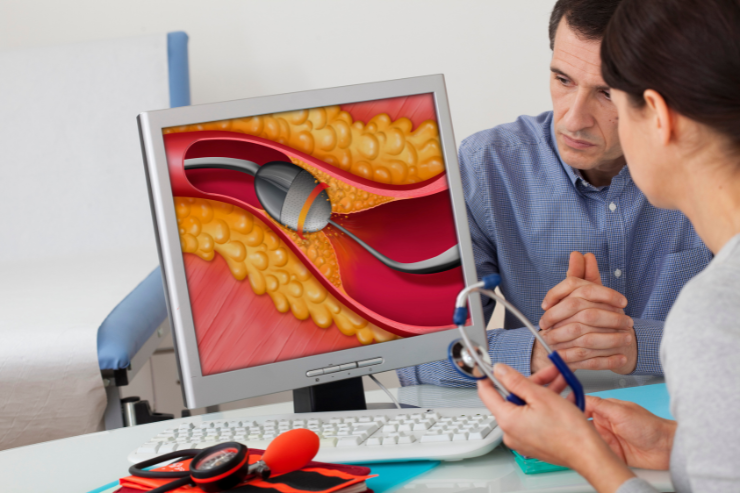

Rotablation

Rotablation is an advanced interventional procedure used to treat heavily calcified and hardened blockages in coronary arteries. It involves a tiny, rotating burr that grinds away tough plaque, creating a smoother path for blood flow. This technique is often used in conjunction with angioplasty and stenting to ensure the arteries are adequately opened, improving heart function and reducing symptoms.

Orbital Atherectomy

Orbital Atherectomy is a specialized procedure used to treat calcified and complex blockages in coronary arteries. It involves a rotating, diamond-coated device that sands down the hardened plaque, improving blood flow. This technique is particularly useful for difficult lesions that are resistant to conventional angioplasty, often used in combination with other interventions to achieve better outcomes.